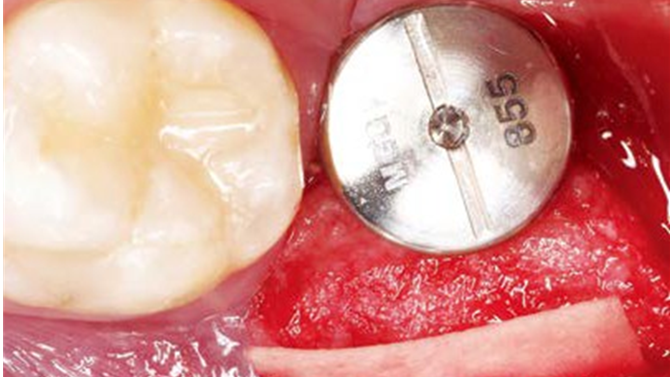

“AnyRidge implant enables fast and stable

osseointegration at this extreme case of bone defect. ”

Clinical case: Bone filling into the bottom of deepest thread at 8.0mm AnyRidge fixture

- Courtesy of Dr. Kwang Bum Park -

Keywords

AnyRidge, Knifethread ,extraction socket, ,initial stability ,Allograft, ,osseointegratio ,Dr. Kwang Bum Park, , Mandibular, Single replacement, AnyRidge, Mega-oss,

Products used

Implant system-AnyRidge, Regeneration-Mega-Oss